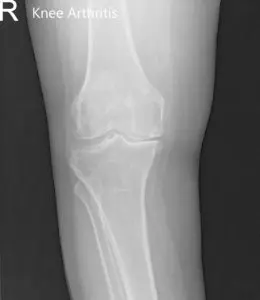

Imaging revealed severed tricompartmental osteoarthritis of the bilateral knee (right greater than left) with osteophytes and medial joint space reduction.

Preoperative X-ray of the right knee showing AP and lateral views